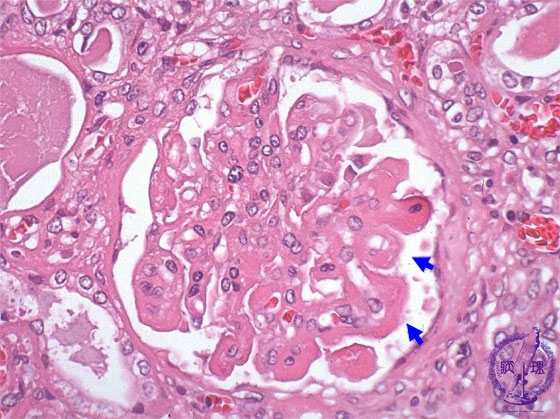

- (6)Lupus Glomerulonephritis

Microscopic findings ( HE, high power view): The basement membrane is markedly thickened and the classic wire-loop lesion is seen (blue arrows). There is focal mesangial cell proliferation.